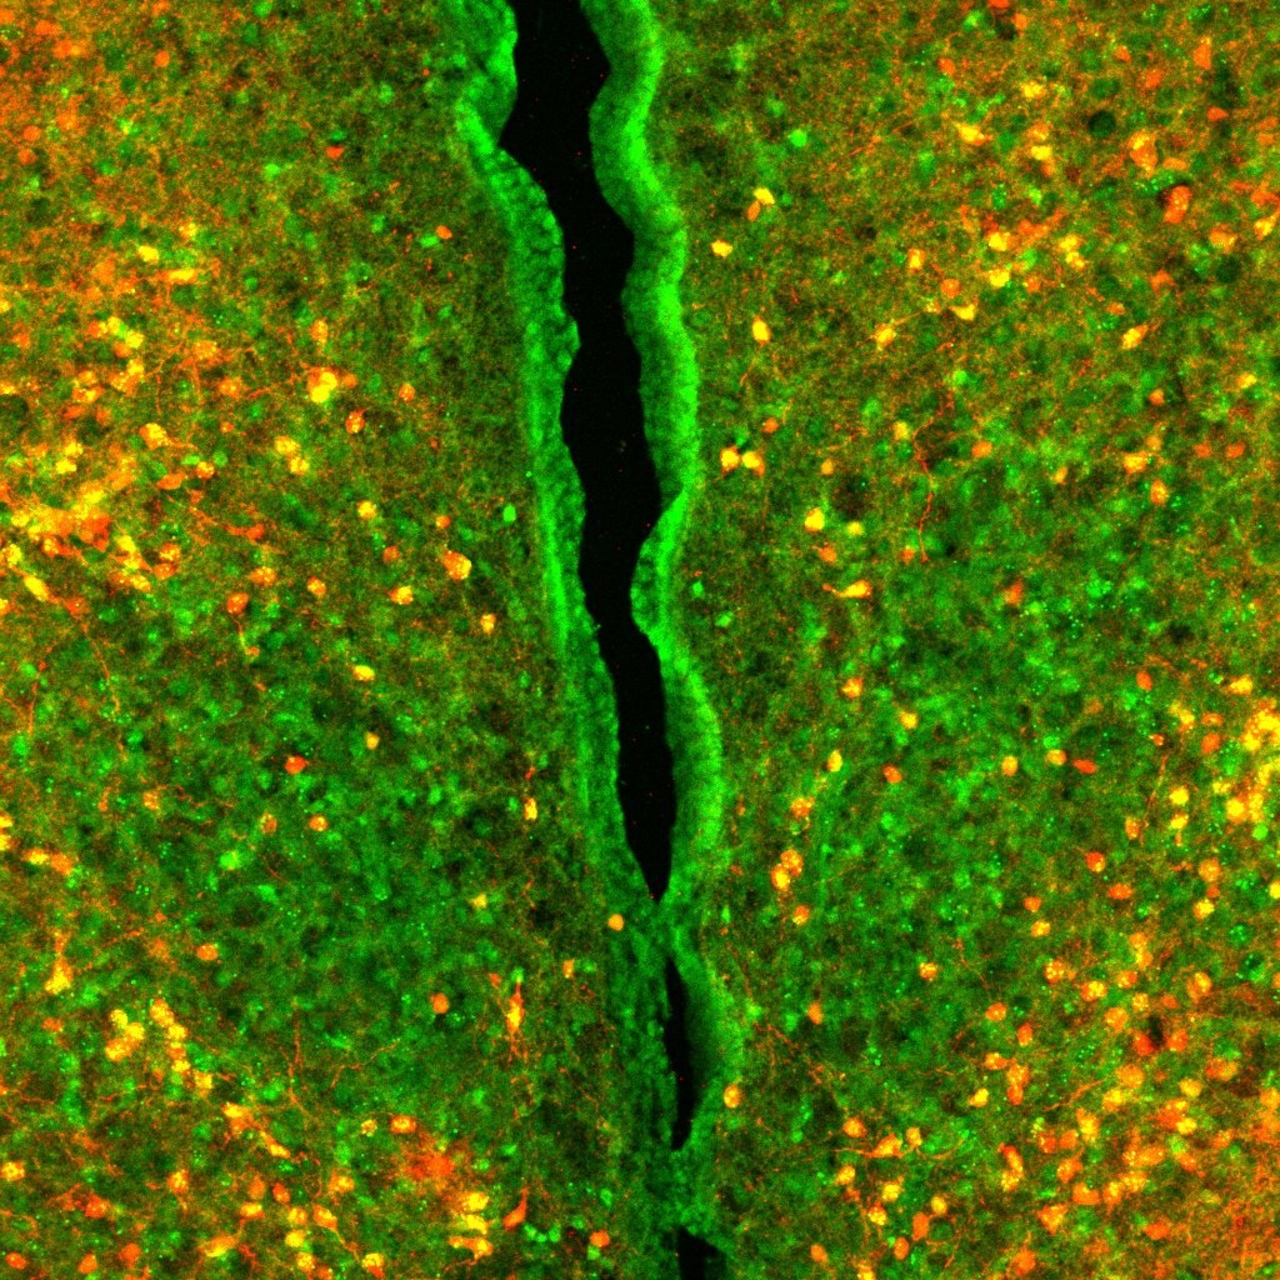

We've developed a unique mouse behavioral assay to investigate caloric nutrient sensing, utilizing sophisticated animal models to uncover the neural circuits influenced by cutting-edge Glp1-R agonist weight-loss drugs. Through these methods, we explore food preferences within the energy density spectrum, pinpointing the specific neuronal circuits impacted by Glp1-R small molecule agonists. Our comprehensive approach involves advanced behavioral and physiological phenotyping, enabling us to discern neuronal circuits activated by the need to eat versus the desire to eat. Notably, when examining mice raised on energy-enriched diets with diverse macronutrient calorie sources, we observed suboptimal performance in our tests. This outcome underscores the detrimental impact of prolonged consumption of specific sugars and fats on calorie sensing. Importantly, our findings highlight the reversible nature of this impairment, demonstrating that exercise and calorie restriction can effectively restore normal calorie sensing function. This breakthrough enhances our understanding of caloric nutrient sensing while offering valuable insights into interventions to mitigate the adverse effects of particular dietary patterns on metabolic health. In essence, our research not only delves into mice behavior and drug effects but also sheds light on how diets can disrupt our ability to gauge fullness and how lifestyle changes might help.

Molecular connectomics reveals a glucagon-like peptide 1 sensitive neural circuit for satiety AN Webster, JJ Becker, C Li, DC Schwalbe, D Kerspern, EO Karolczak, ... bioRxiv, 2023.10. 31.564990